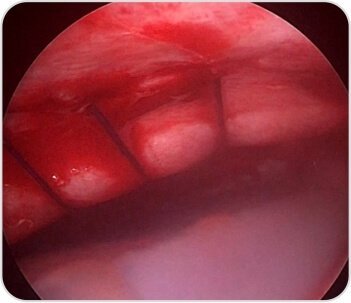

7th & 8th Rib intercostal muscle tear with hematoma and lung herniation